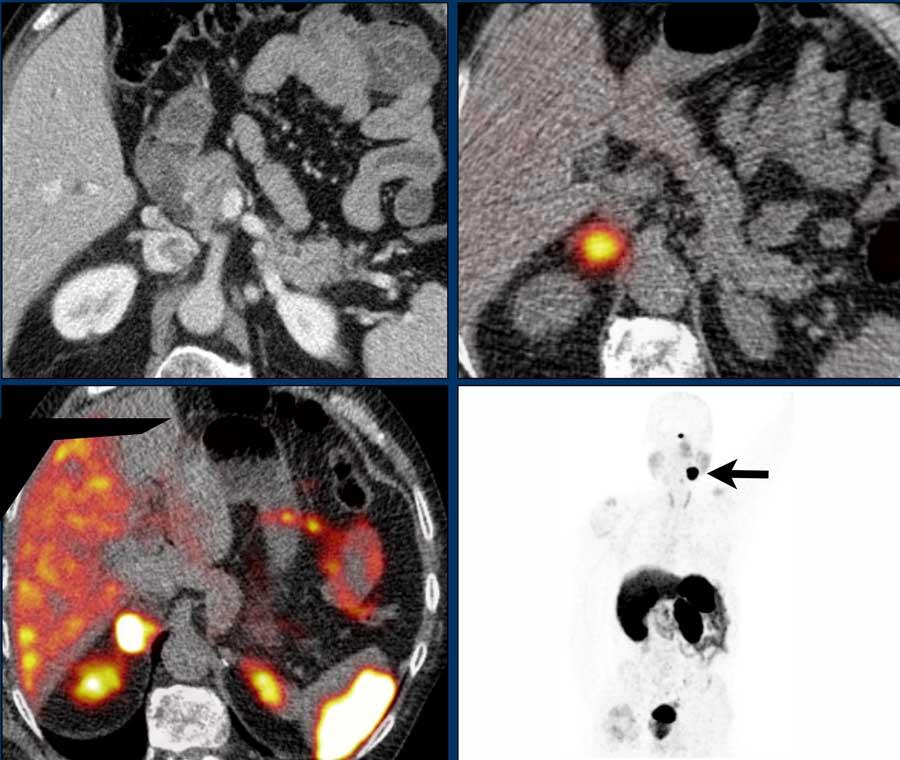

Hình ảnh phía trên bên trái là CT tầm soát thì tĩnh mạch ở bệnh nhân có đột biến gen SDHD đã biết, liên quan đến nguy cơ cao phát triển u tủy thượng thận và u cận hạch.

Có một khối u tuyến thượng thận phải tăng sinh mạch máu.

SPECT MIBG được thực hiện cho thấy sự hấp thu mạnh, giúp xác nhận chẩn đoán u tủy thượng thận.

Một năm sau, tầm soát được thực hiện bằng PET-CT 68 Ga-DOTATATE.

Hình ảnh cho thấy sự hấp thu mạnh ở tuyến thượng thận phải, đồng thời cũng ghi nhận sự hấp thu mạnh tại một khối u cầu cảnh (glomus caroticum) bên trái như thấy trên ảnh MIP mặt phẳng đứng dọc bên phải.

Sự hấp thu DOTATATE ở lách và tuyến yên là bình thường, cũng như sự bài tiết bình thường qua thận xuống bàng quang.